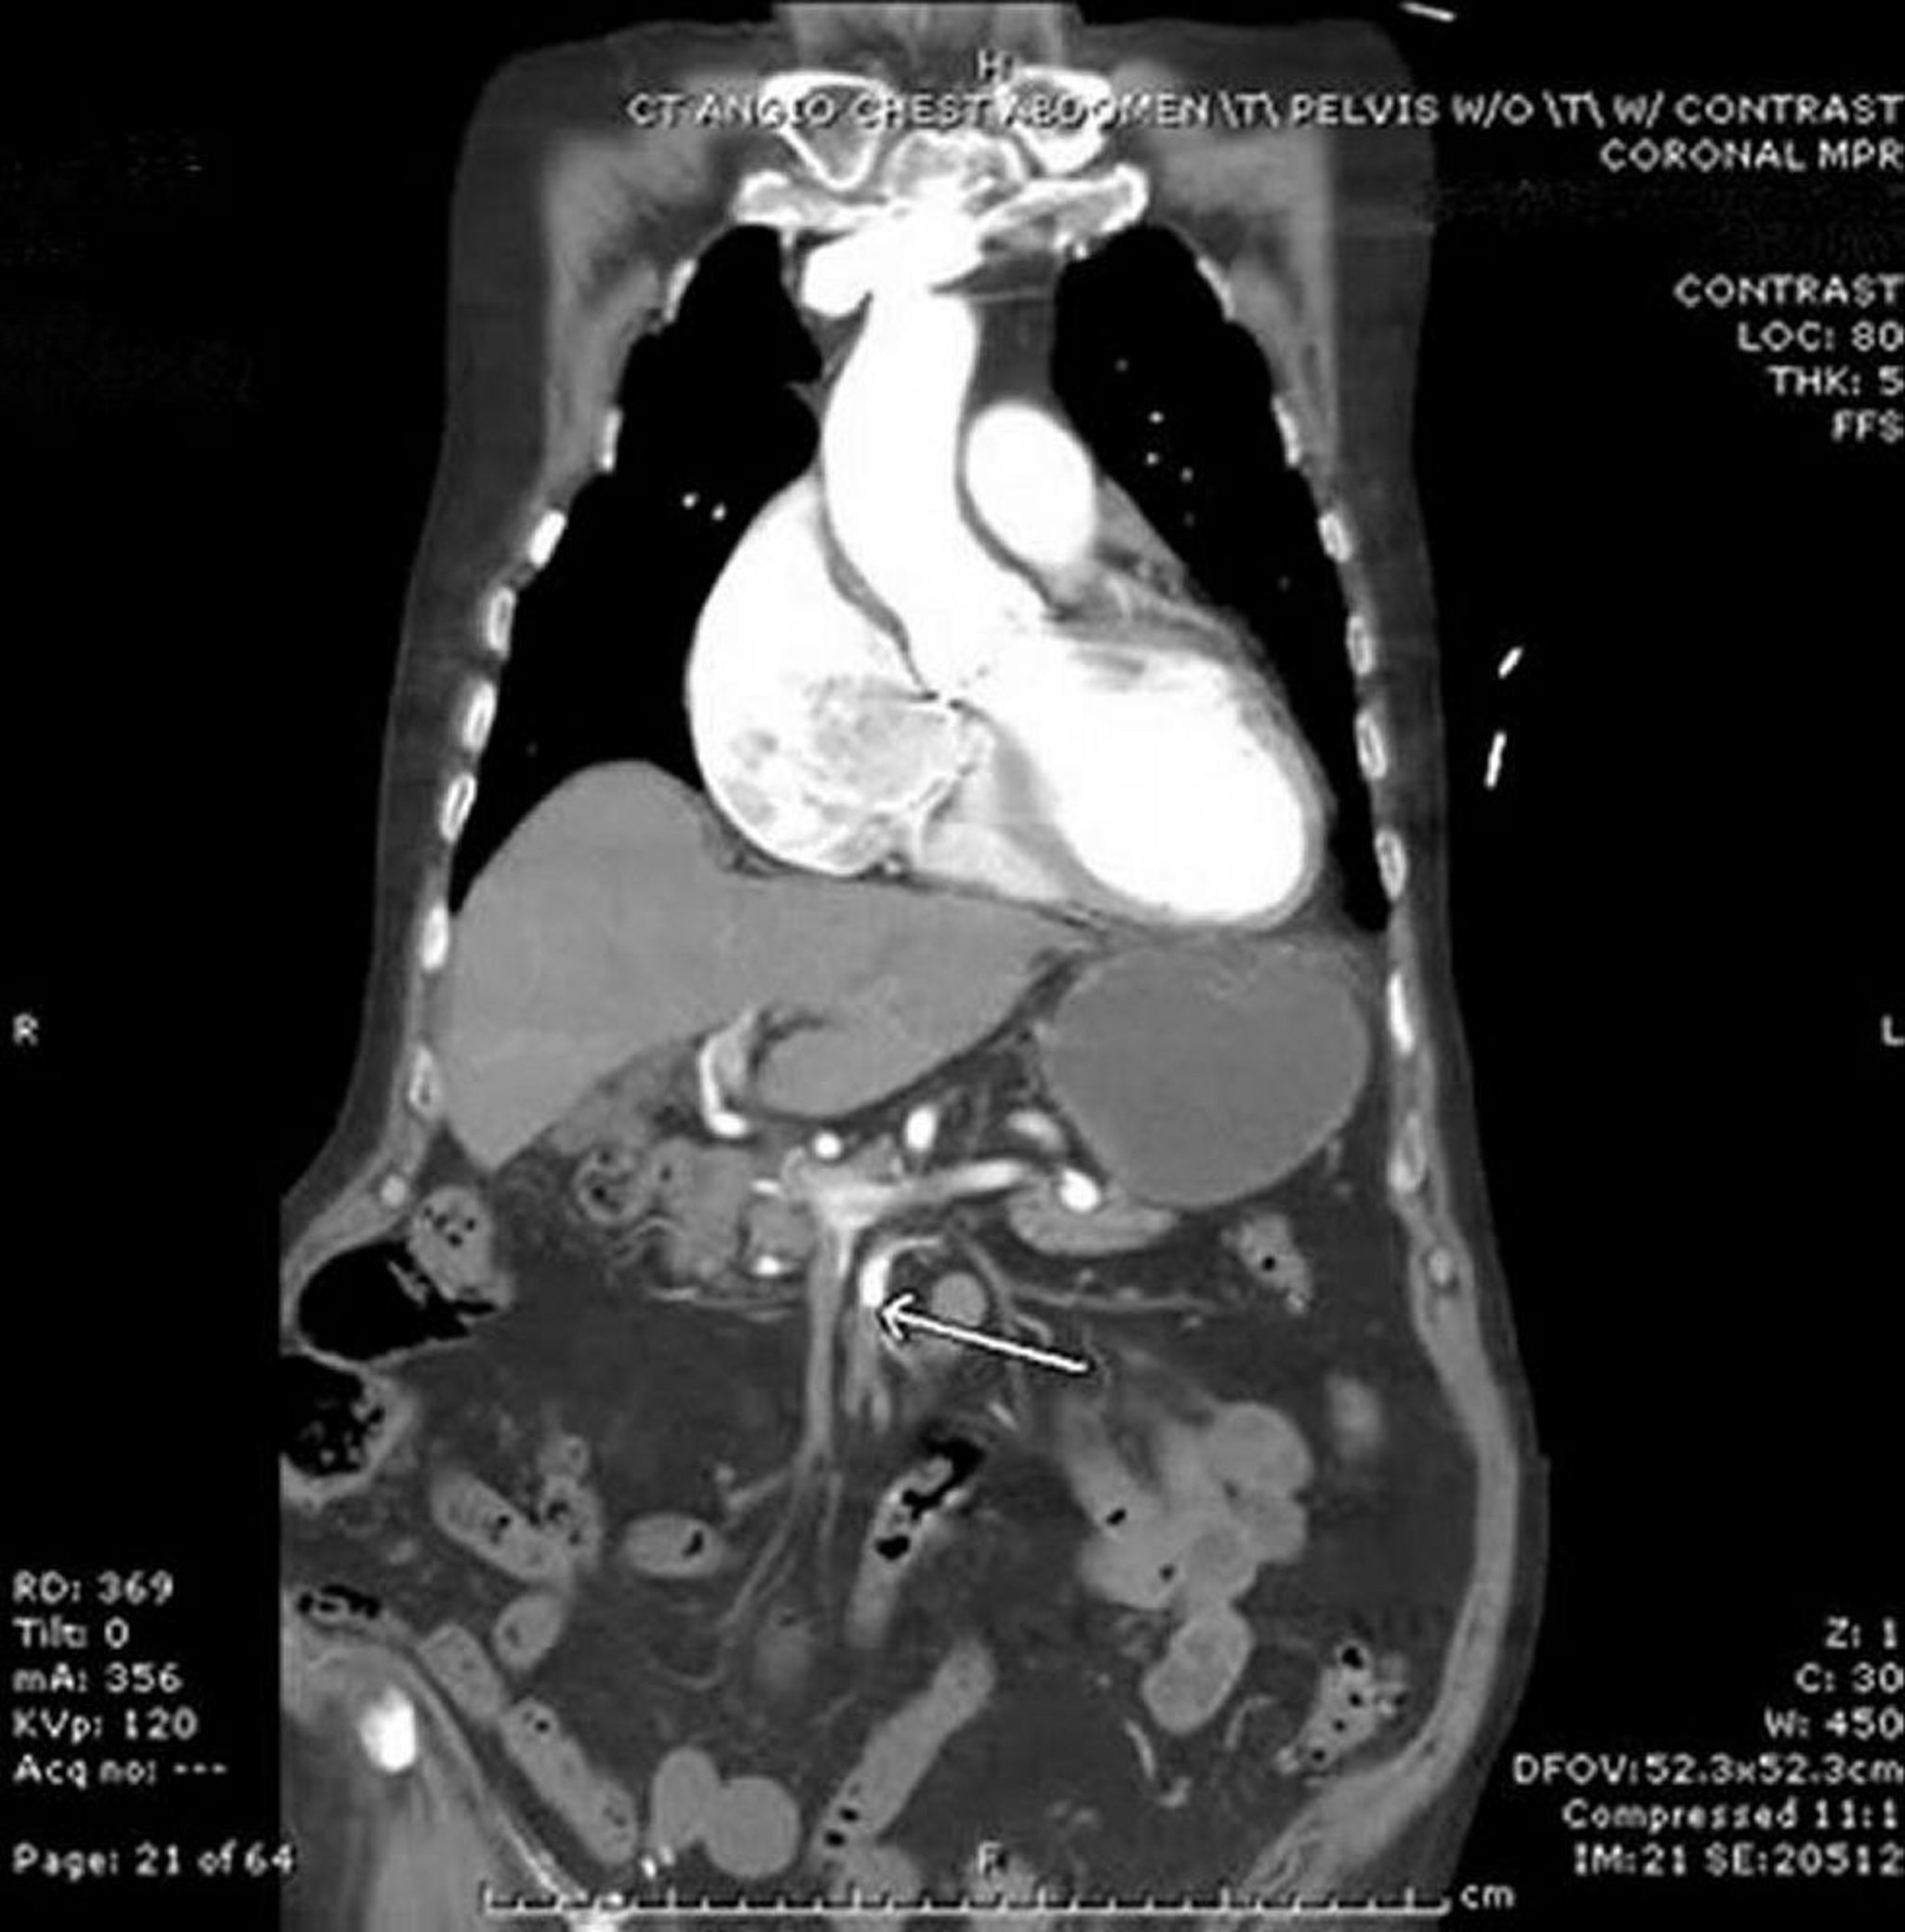

Мезентериальная ишемия (КТ-ангиография)

На этом изображении стрелка указывает на верхнюю брыжеечную артерию с резкой границей введенного внутривенно контраста. Наблюдается некоторое утолщение тонкой кишки в левой части брюшной полости. Данный случай эмболии представляет собой нарушение со стороны сердца у пациента с мерцательной аритмией.

Image provided by Parswa Ansari, MD.